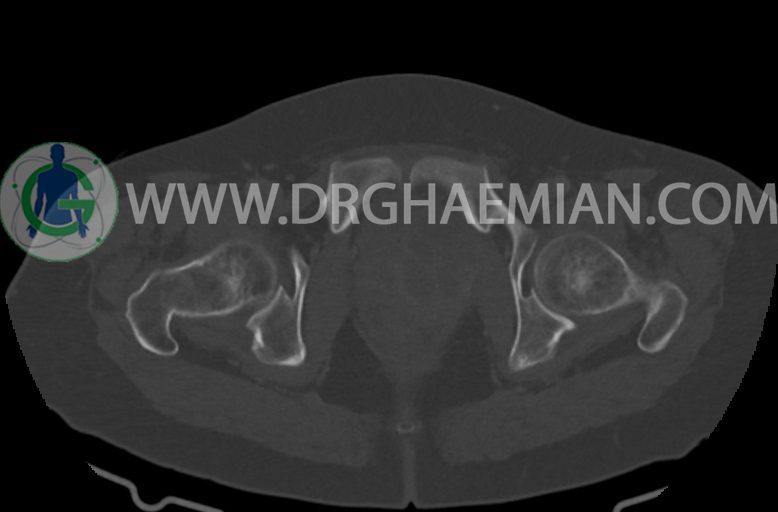

در سی تی اسکن اسپیرال ریه ها و مدیاستن ، شکم و لگن با و بدون کنتراست وریدی (مولتی دیدکتور 16 با مقاطع ظریف و بازسازی کرونال):

–ساختار Cystic multiseptate همراه با Enhancing thick septation به ابعاد 79x62mm در

لگن دیده می شود که در درجه اول مطرح کننده ی ضایعات نئوپلاستیک تخمدانی نظیر mucinous cyst adenocarcinoma است.

–شواهد هیسترکتومی

–ضایعه ی mass like هیپردنس- هتروژن به قطر 42mm در سمت راست لگن